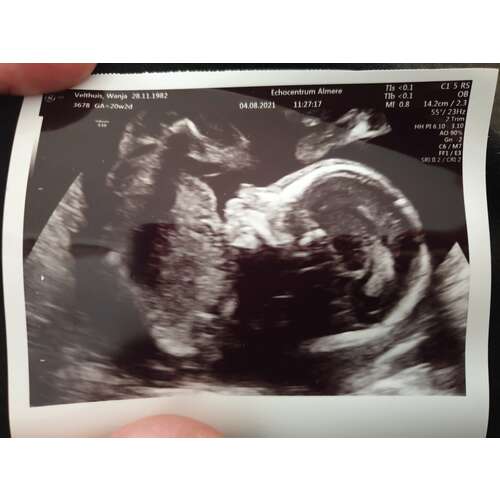

Hier inmiddels de 38wkn voorbij en Ukkie heeft zowat alle mogelijke standjes gehad hoor 😅 Zeker rond de 20wkn echo hebben die kleintjes nog zoveel ruimte dat het blijkbaar heerlijk is om met je tenen je voorhoofd te kriebelen 😋

Wij moesten trouwens ook voor een 2e keer terug omdat de 1e x 20wkn echo niet volledig lukte. Ukkie lag in stuit, met kontje in mijn bekken en de teentjes tegen het voorhoofd. Had ook geen zin om een andere houding aan te nemen, dus een paar dagen later terug voor een herkansing. Toen was het net kantje boord dat het lukte om alles te bekijken 😅

zo lag ze echt heel vaak in m'n buik 🤣 dacht ik ligt toch niet lekker. Soms moest ik dan gaan staan of goed lachen dan draaide ze soms 😉 succes en veel plezier maandag 💞

Dat heet een onvolkomen stuitligging. Perfect normaal op deze zwangerschaps leeftijd, ze kunnen nog lekker alle kanten uit. ☺️